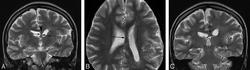

Диагноз ГМЭ в современных условиях устанавливается, в подавляющем большинстве случаев, при МРТ исследовании головного мозга. МРТ у больных с ГМЭ выявляет асимметрию гемисфер за счет диффузно увеличенного, аномального полушария. Характерна вентрикуломегалия диспластичной гемисферы. В Т2 - режиме выявляется интенсивный сигнал в белом веществе - результат сочетания глиоза и участков гипомиелинизации.